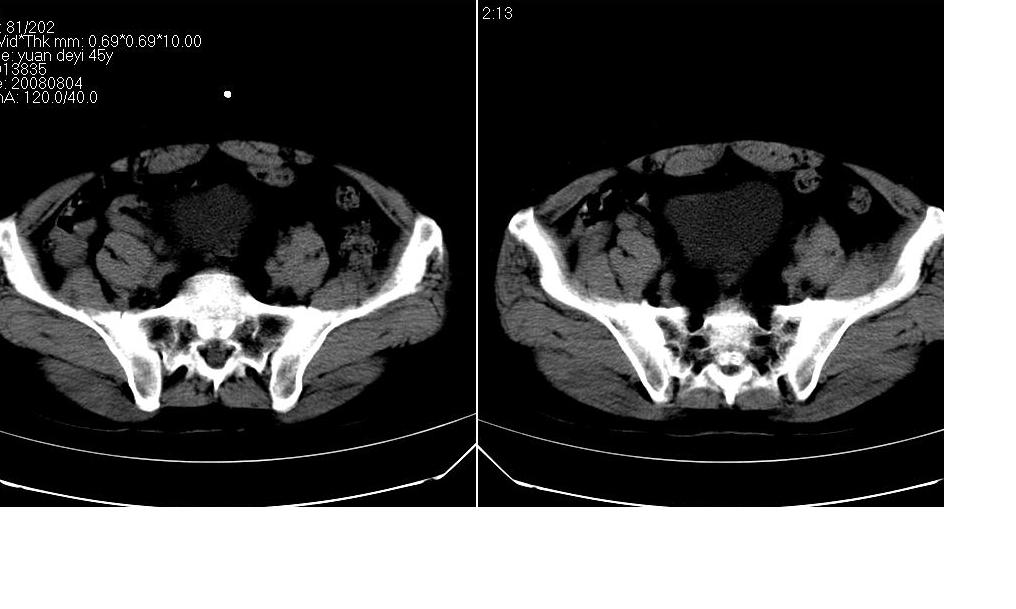

标题: CT14990:M45Y,盆腔CT平扫

男 45岁,05年在外医院行膀胱癌手术,近期发现腹壁包块.

考虑膀胱癌术后切口种植转移。

结合病史支持考虑膀胱癌术后切口种植转移。